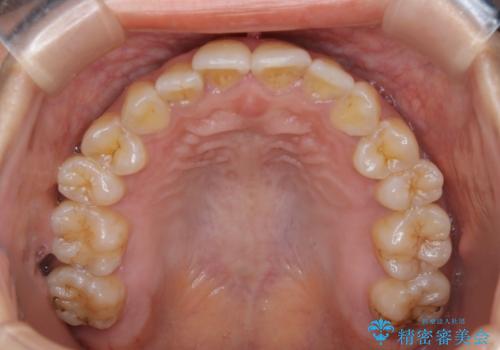

前歯を後ろに下げたい ワイヤー矯正(クリア装置)

- 前歯を後ろへ下げることを主訴に来院された患者様です。

10代の時に非抜歯でワイヤー矯正をしていました。

口元の突出感の改善や歯の移動量などを考慮し、抜歯を伴うワイヤー矯正での治療を選択しました。

抜歯を行うことで前歯を後ろへ下げるスペースを獲得し、口元の突出感や歯のガタつきを改善していきました。